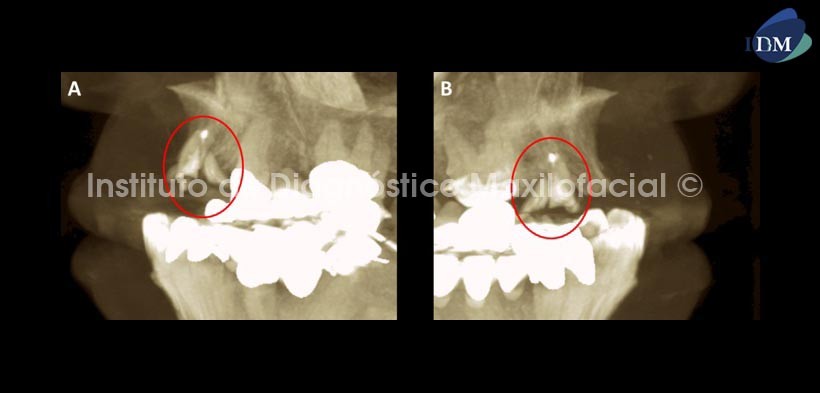

En cortes axiales (Fig.3) se señala el proceso osteolítico perirradicular a nivel del tercio apical (flecha roja), así mismo se ha señalado el trayecto de la fractura en los tercios medio y cervical (flechas azules), pudiendo notar la disposicion vestibulo-palatina de esta y el compromiso del conducto radicular. Se muestra tambien el tratamiento de conducto realizado en dicha pieza.